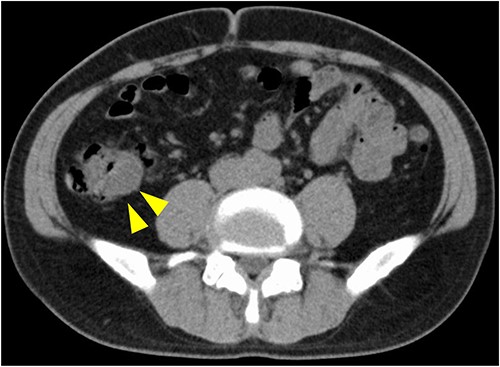

A 50-year-old man was examined at a local hospital for an annual check-up, and colonoscopy revealed an SMT-like lesion near the ascending colon. Due to this finding, the patient was referred to our hospital for further testing and treatment. He had no significant medical history or abnormal laboratory data, and physical examination findings were unremarkable. Colonoscopy confirmed the presence of SMT-like lesion in the ascending colon, while the cecum and Bauhin valve appeared normal. A cystic lesion in the intestinal wall was discovered on endoscopic ultrasonography (Fig. 1). Contrast-enhanced computed tomography (CT) also revealed the same lesion near the ascending colon, measuring 15 mm in diameter, with unclear continuity and no evidence of swollen lymph nodes (Fig. 2). Based on these findings, our preoperative diagnosis was an ascending colon SMT. Differential diagnoses included an appendiceal tumor and colon cancer. We planned to dissect the tumor for definitive diagnosis and treatment. However, endoscopic submucosal dissection is difficult for differential diagnoses.

CT image. An iso-density lesion in the ascending colon (arrowhead).